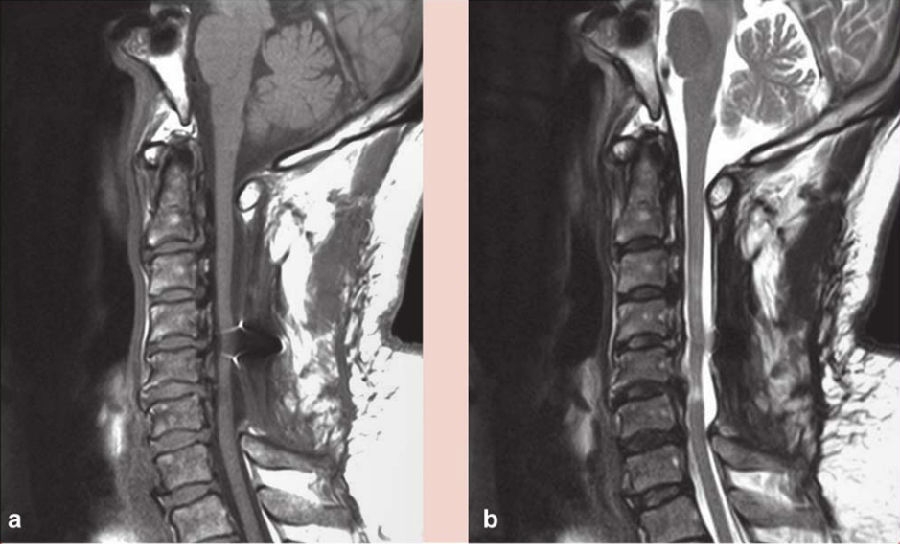

术前磁共振(MRI)示:C3-6颈段脊髓内可见散在条片状稍长T2信号影,以C5-6节段为著,C4-6段脊髓稍变细。C2-6后纵韧带不规则增厚,呈条状短T2信号影,相应段硬膜囊受压,局部压迫颈髓,相应硬膜囊前后径稍变窄。

术后给予激素、补液及支持对症治疗,右手麻木较前好转,右侧肢体出现无力,左侧肢体出现麻木,疼痛感不明显,经康复治疗后,右手环指及小指仍感无力,余肢体麻木及无力较前好转,仍对生活及工作有影响。复查颈椎磁共振(MRI)示:C2-6椎板减压及内固定术后状态(图2),C4-6脊髓稍变细,以 C5-6节段显著,C2-6后纵韧带钙化(图2);CT三维重建钉棒系统位置良好(图3);术后3个月复查磁共振(MRI),髓内异常信号较前缩小,颈椎生理曲度变直(图4);术后11个月复查磁共振(MRI)示C4-5、C4-6椎间盘突出,脊髓受压明显,颈椎生理曲度进一步变直(图5)。

图2 术后1周磁共振(MRI)示C4-6脊髓稍变细,髓内可见变性信号

a. T1像;b. T2像

图5 术后11个月磁共振(MRI)示C4-5、C4-6椎间盘突出,脊髓受压明显

a. 矢状位T1像;b.矢状位T2像